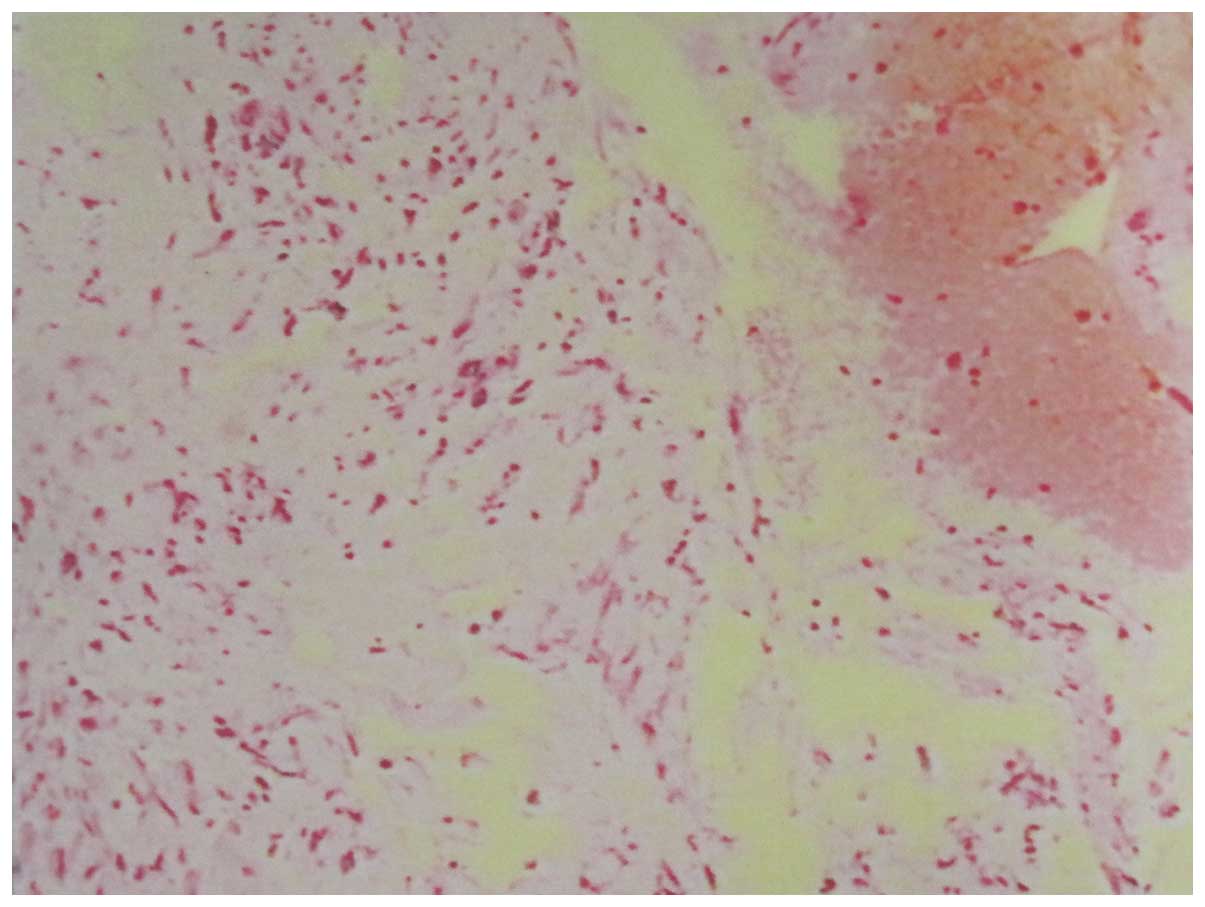

that no distant metastases had occurred (Fig. 3). Chest CT did not demonstrate any

thoracic abnormality and the CT-guided biopsy results showed blood

clots as well as a small quantity of heterogeneous cells (Fig. 4). Therefore, the clinical diagnosis

was a malignant bone tumor, with the most likely diagnosis

considered to be an osteosarcoma, as a primary bone tumor.